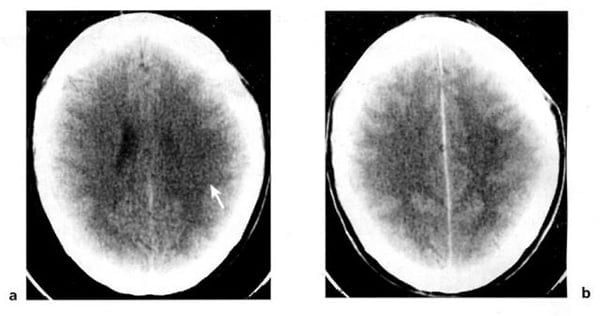

Hình 1.29. U tế bào hình sao độ 2. Ở vùng đỉnh thái dương sau bên trái (mũi tên). Bệnh nhân nam 40 tuổi. Trước tiêm, mật độ hai bên hơi bất xứng, mơ hồ (a). Sau tiêm, không thấy bắt chất cản quang (b). XQCLĐT thường âm tính. U hiện rõ trên CHT.